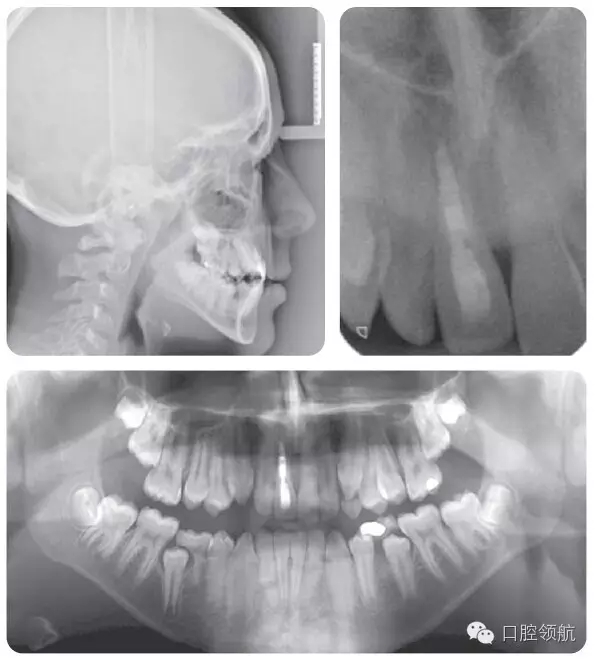

牙根外吸收可以通過牙齒的松動(dòng)度來判斷。在一些病例可能發(fā)生根骨粘連,并且牙齒位置較鄰牙常表現(xiàn)為未能萌出至平面。叩診該患牙呈高調(diào)、濁音。正畸力往往難以使該牙產(chǎn)生移動(dòng)。臨床和X線片檢查(圖2.47)顯示該患者的UR1發(fā)生了根骨粘連。

● UR1根骨粘連,牙冠變色。